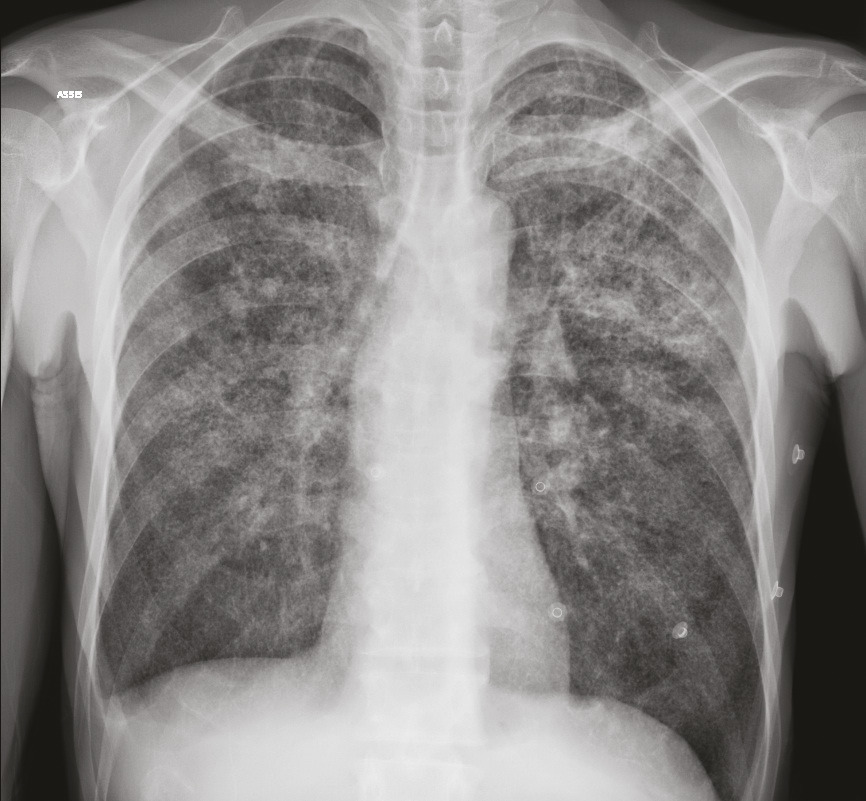

Cet homme était hospitalisé pour une fièvre avec toux et expectorations sans hémoptysie. On notait à l’examen de discrets ronchus et des adénopathies cervicales. Le bilan biologique montrait une hypercalcémie avec hypoparathyroïdie ; la 25(OH)-vitamine D3 était normale et la 1,25(OH)2-vitamine D3 augmentée. La radiographie pulmonaire et la tomodensitométrie thoracique mettaient en évidence des séquelles parenchymateuses d’une probable tuberculose et un aspect de miliaire. L’examen direct des crachats trouvait des mycobactéries et la culture confirmait la présence de Mycobacterium tuberculosis. L’évolution de la calcémie était favorable après hydratation, corticothérapie et quadrithérapie antituberculeuse.